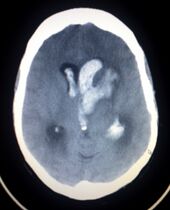

السكتة النزيفية Hemorrhagic stroke

CT scan showing an intracerebral hemorrhage.

سكتة نتيجة نزيف في المخ:

أو نزيف داخل المخ Intracerebral haemorrhage